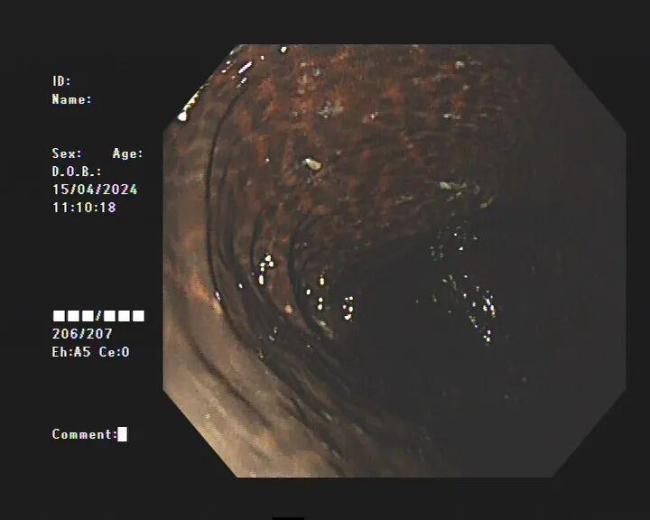

手术台上,医生切开腹腔时倒吸一口冷气——她的一段结肠已经失去弹性,肠壁像被墨水浸泡过一样,呈现骇人的黑色。长期服用刺激性泻药导致肠壁色素沉积,神经末梢坏死,肠道再也无法自主蠕动。最终,廖女士被切除了30厘米的肠管。术后醒来,她看着肚子上的伤口,哭得说不出话。“如果十年前,我能早点去医院看看就好了……”

直到2024年4月中旬,季女士发现所有的通便茶都不管用了,腹部持续胀痛,才到医院就诊。检查结果显示,她的整条大肠内壁呈现出棕黑色蛇皮样,黑色素沉着明显,被诊断为“结肠黑变病”。若继续发展,有癌变的可能。经过治疗,季女士的便秘症状有了明显的好转。

临床上许多患者自行口服药物后筛查肠镜,均有不同程度的结肠黑变病。正常的结肠黏膜是淡红色的,看起来光滑平坦,黏膜表面的小血管纹理清晰可见。而结肠黑变病的肠黏膜色泽呈现棕色、褐色,有豹纹或者蛇皮一样的条状纹,严重的甚至会变成黑色。